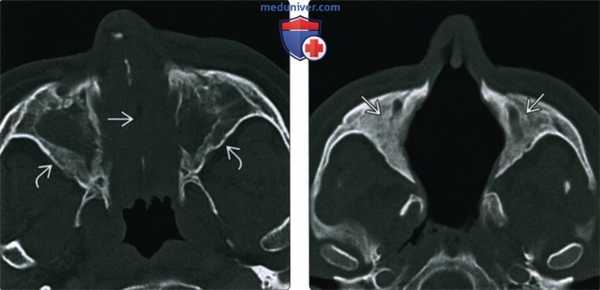

(Слева) При аксиальной «костной» КТ определяется узловой мягкотканный компонент, заполняющий полость носа; снижена пневматизация верхнечелюстных пазух. Носовая перегородка перфорирована, стенки пазух утолщены и склерозированы, что типично для ГПА.

(Справа) При аксиальной «костной» КТ в случае далеко зашедшего ГПА определяется тотальная центральная деструкция полостей носа, включая перегородку, раковины, наружные стенки. Верхнечелюстные пазухи блокированы утолщенной костью.

2. КТ носа, пазух при гранулематозе Вегенера с полиангиитом:

• КТ без КУ:

о Хронический риносинусит с локальными узлами в слизистой оболочке и объемными образованиями в полости носа

о Инфильтрация периантральных тканей

о Орбита часто становится первоочередной зоной инвазии

о Реже поражается основание черепа, крылонебная ямка, ретромаксиллярная область, носоглотка

• КТ с КУ:

о Узловое и опухолевидное утолщение слизистой оболочки с накоплением контраста

• «Костная» КТ:

о Хроническая обструкция и воспаление пазух могут вызывать неспецифический гиперостоз их стенок

о Эрозии костей/хрящей часто вначале локализуются в носовой перегородке, приводя к перфорации

о Деструкция носовых раковин и наружной стенки носа (крючковидного отростка и внутренней стенки пазухи)

о Возможно поражение твердого неба и формирование синоназально-оральной фистулы